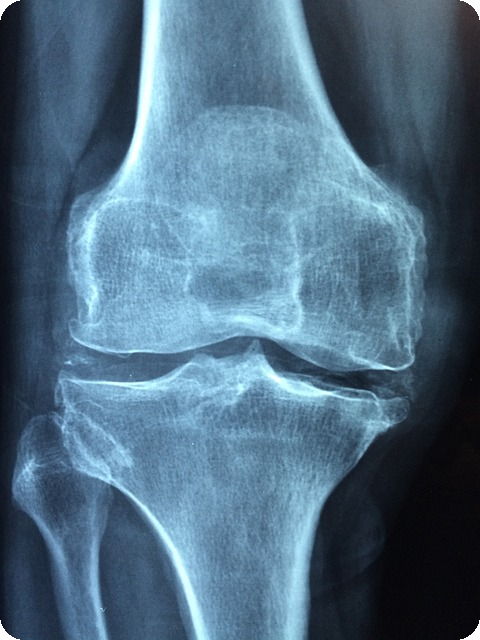

무릎 건강의 중요성

무릎은 우리의 일상에서 가장 중요한 역할을 하는 관절 중 하나입니다. 이 섹션에서는 무릎의 역할과 기능, 관절 손상의 원인, 무릎 건강 신호, 그리고 미리 예방할 수 있는 방법에 대해 살펴보겠습니다.

무릎의 역할과 기능

무릎은 걷기, 뛰기, 앉기 등 다양한 움직임에 필수적인 역할을 합니다. 이 관절은 체중을 지탱하고, 매일 반복되는 행동에서 지대한 영향을 미칩니다. 따라서 무릎 건강이 좋지 않으면 일상적인 활동이 어려워질 수 있습니다. 무릎과 관련된 연골은 체중이 실리는 부위로 작용하여 작은 자극에도 쉽게 손상될 수 있습니다.

"무릎이 아프기 시작하면 삶의 질 자체가 떨어지게 된다."

관절 손상의 원인

무릎 연골 손상의 주요 원인에는 다음과 같은 것들이 있습니다:

무릎 건강 신호

무릎 건강에 문제가 생기면 몇 가지 신호가 나타납니다. 다음과 같은 증상을 주의 깊게 살펴보아야 합니다:

- 통증: 무릎을 구부릴 때 통증이 느껴질 수 있습니다.

- 소리: 걸을 때 '딱딱' 소리가 나는 경우가 있습니다.

- 붓고 뻣뻣함: 특히 아침에 무릎이 뻣뻣한 느낌이 든다면 염증이 생겼을 수 있습니다.

이러한 신호는 무릎 건강 관리가 필요하다는 최선의 경고입니다.